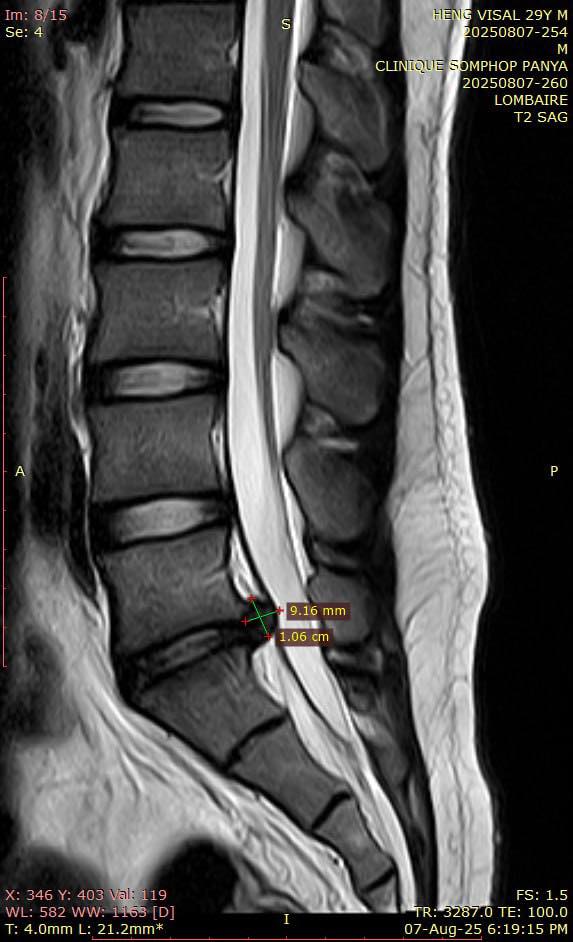

តាមការឱ្យដឹងបន្ថែមពីភរិយារបស់លោកនាពេលនេះអ្នកផលិតមាតិកា ហេង វិសាល មានបញ្ហាលៀនឌីសឆ្អឹងខ្នង ដែលបញ្ហានេះធ្វើឱ្យលោកឈឺចង្កេះខ្លាំង និងពិបាកក្នុងការធ្វើចលនាដើរឬអង្គុយ។ ស្ថានភាពសុខភាពរបស់អ្នកផលិតមាតិកាប្រុសរូបនេះធ្វើឱ្យភរិយានិងក្រុមគ្រួសាររបស់លោកមានការបារម្ភជាពន់ពេក។ ក្នុងនោះដែរ បណ្ដាអ្នកគាំទ្ររបស់លោកបានបង្ហាញក្ដីបារម្ភព្រមទាំងបានជូនពរឱ្យលោកឆាប់ជាសះស្បើយនិងទទួលបានសុខភាពល្អដូចដើម។

រូបភាព ៖ Sreynea